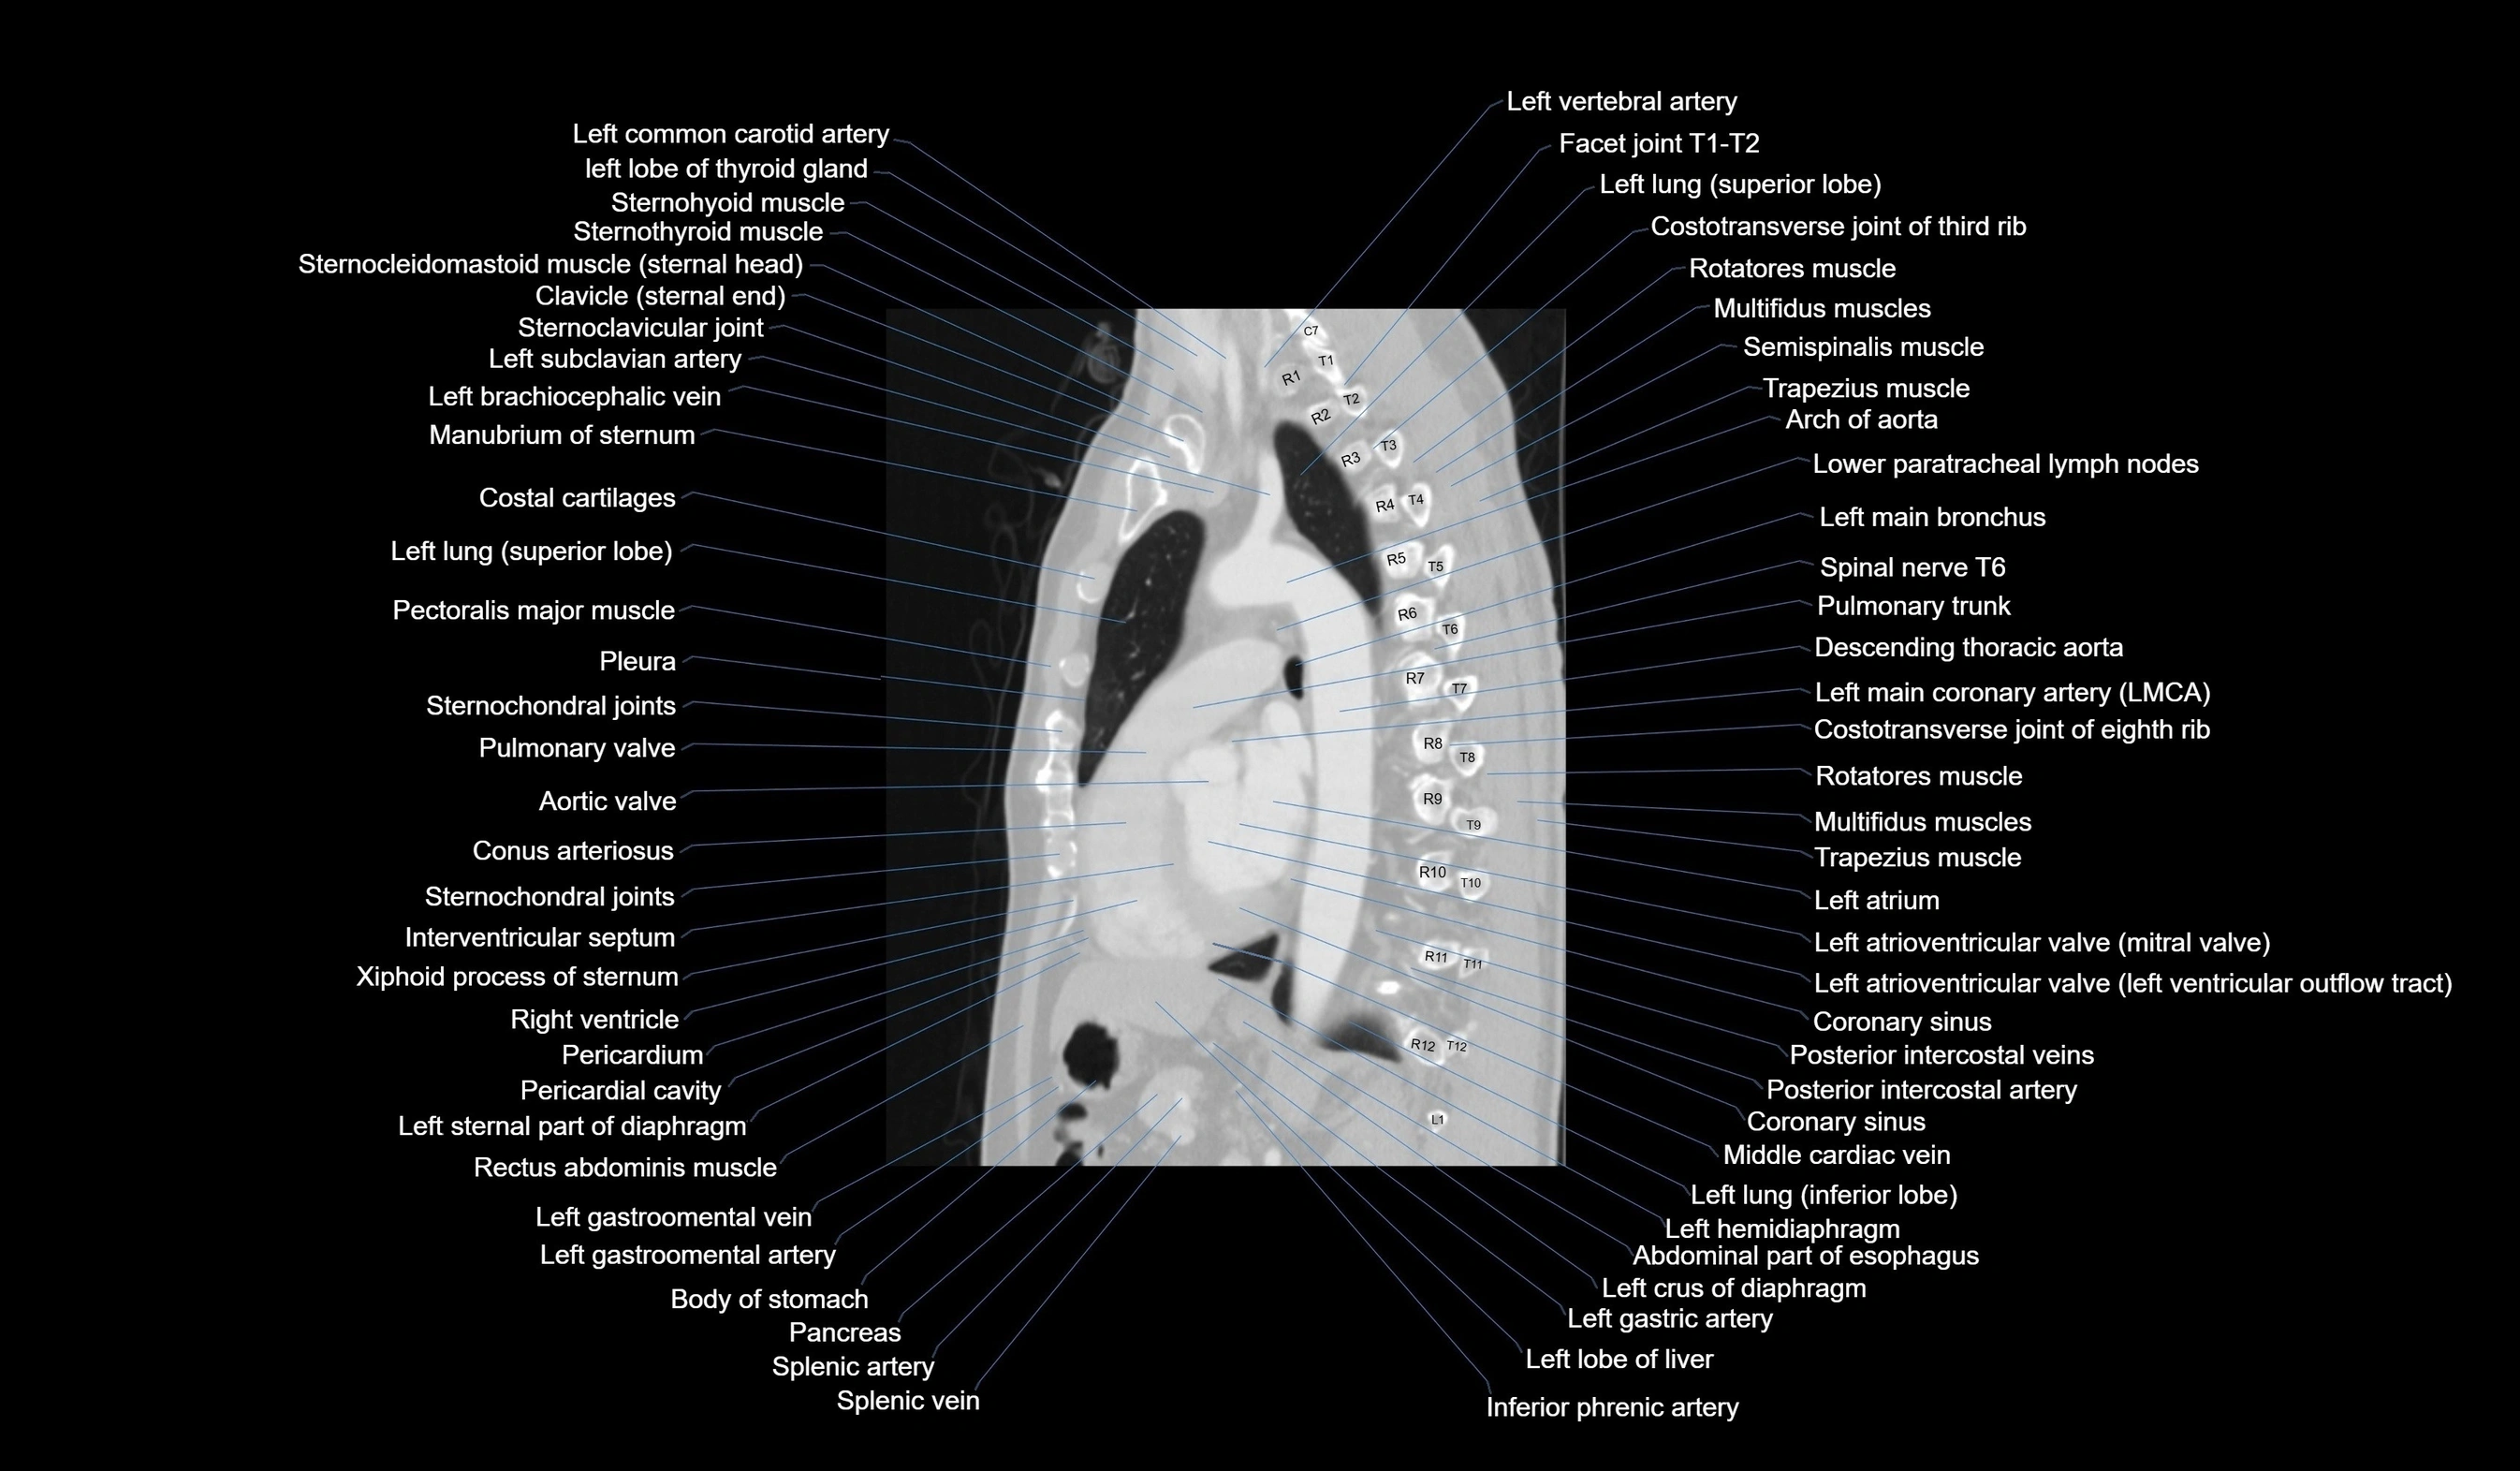

- T (Thoracic spine)

CT images